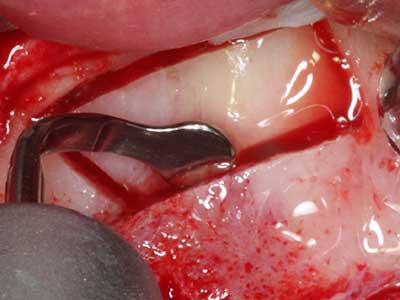

Bei der Knochenblockentnahme zeigen sich weitere Vorteile für die Piezochirurgie: Neben der bereits beschriebenen hohen Präzision bei der Osteotomie stellt sich gerade die Verwendung der dünnen Sägespitzen als besonders materialschonend heraus. Bei der Verwendung insbesondere von Lindemannfräsen sind mit deutlich höheren Entnahmeverlusten durch die dickere Instrumentenspitze zu rechnen (Lakshmiganthan, Gokulanathan et al. 2012). Die insbesondere bei retromolar entnommenen Blocktransplantaten notwendige basale Abtrennung wird durch speziell hierfür vorgesehene rechtwinklige Sägen erleichtert, so dass die Piezochirurgie als präzises, übersichtliches und sicheres Verfahren zur retromolaren Knochenblockgewinnung angesehen wird (Happe 2007) (Abb. 1-12).